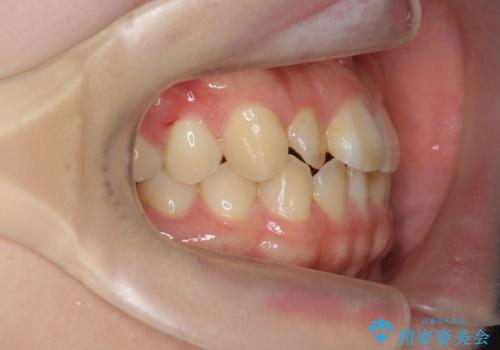

インビザラインを行う前に前歯の部分矯正を行ったことで、しっかりとねじれが取れ整った歯列へと仕上げることが出来ました。